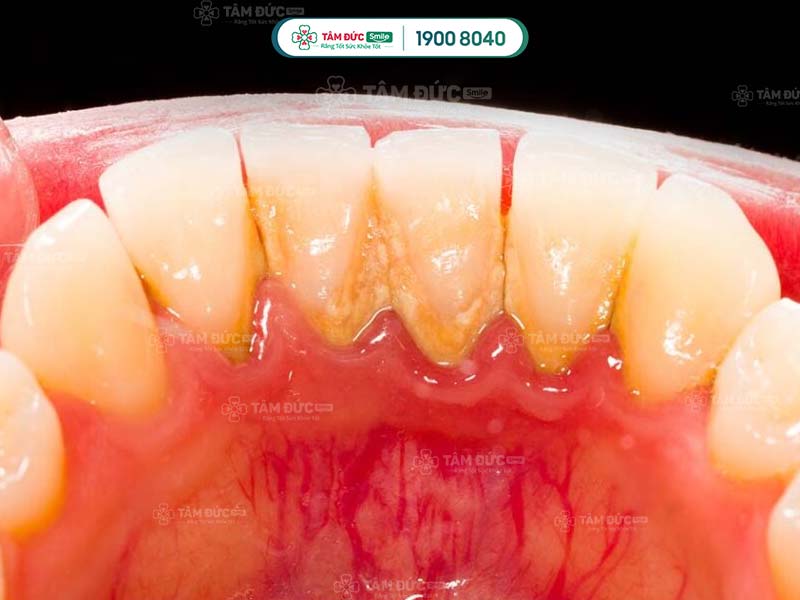

- Phát hiện có nhiều cao răng và mảng bám ở thân răng hoặc dưới nướu.

Cao răng không phải là nguyên nhân trực tiếp gây ra các bệnh lý về răng miệng, nhưng lại là nơi trú ngụ của nhiều loại hại khuẩn. Vì vậy, cao răng tạo điều kiện để vi khuẩn gây bệnh.

Cao răng tích tụ lâu ngày sẽ gây ra các bệnh lý như: Sâu răng, viêm nướu, tụt nướu, mòn men răng, viêm nha chu,... Do đó, cạo cao răng thường xuyên giúp Quý khách ngăn chặn vi khuẩn phát triển, giảm nguy cơ mắc phải các bệnh lý răng miệng.

Vi khuẩn tích tụ trong cao răng thời gian dài sẽ tấn công vào sâu bên trong, làm hư hại răng và nướu nặng nề. Lâu dần, xương hàm của Quý khách có thể bị tiêu biến, tăng nguy cơ lung lay răng vĩnh viễn. Như vậy, cao răng nghiêm trọng có thể làm cho Quý khách đối mặt với vấn đề mất nhiều răng cùng lúc.